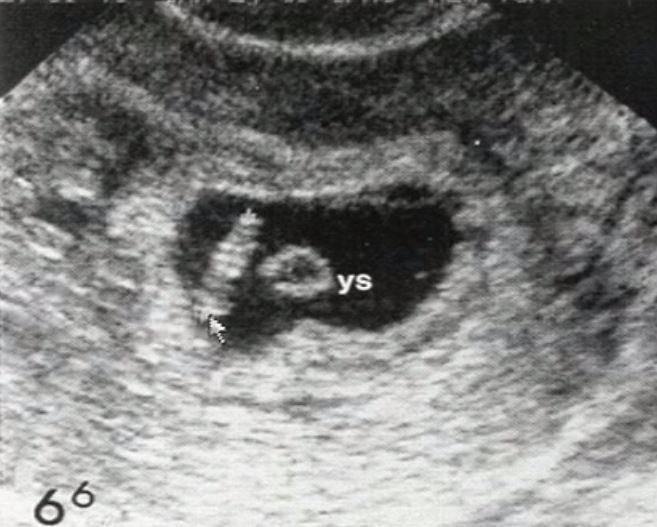

VEamos unos ecos

normal